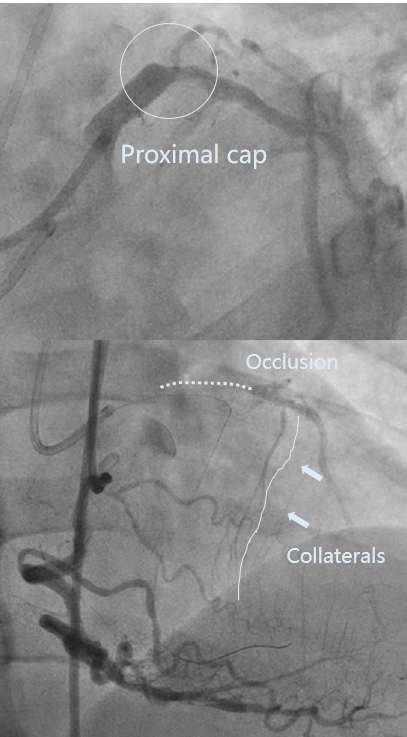

LAD开口全闭、OM开口70%

LAD开口全闭、CTA示LAD严重钙化、RCA重度迂曲、外院尝试两次开通。

LAD pre-IVUS check RUN 1 looking for entry point

CTA示LAD近中段严重钙化、LAD开口无残端、RCA极度迂曲。

首选IVUS找开口、因LM直径达6.5mm,无法看清分支方向。